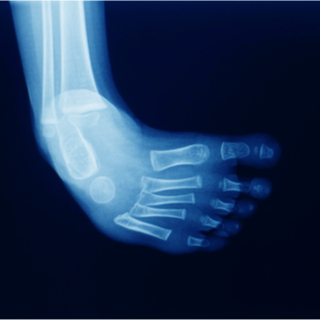

عادة تكون الإصابة بالقدم الحنفاء واضحة عند لحظة الولادة، بالإضافة يمكن الكشف عن هذه المشكلة حتى قبل ولادة الطفل، حيث يمكن تحديدها في منتصف الثلث الثاني من الحمل بواسطة السونار. قد يوصي الأطباء بإجراء بعض الفحوصات التصويرية مثل الأشعة السينية، للتحقق من حالة العظام ومدى شدة الحالة.